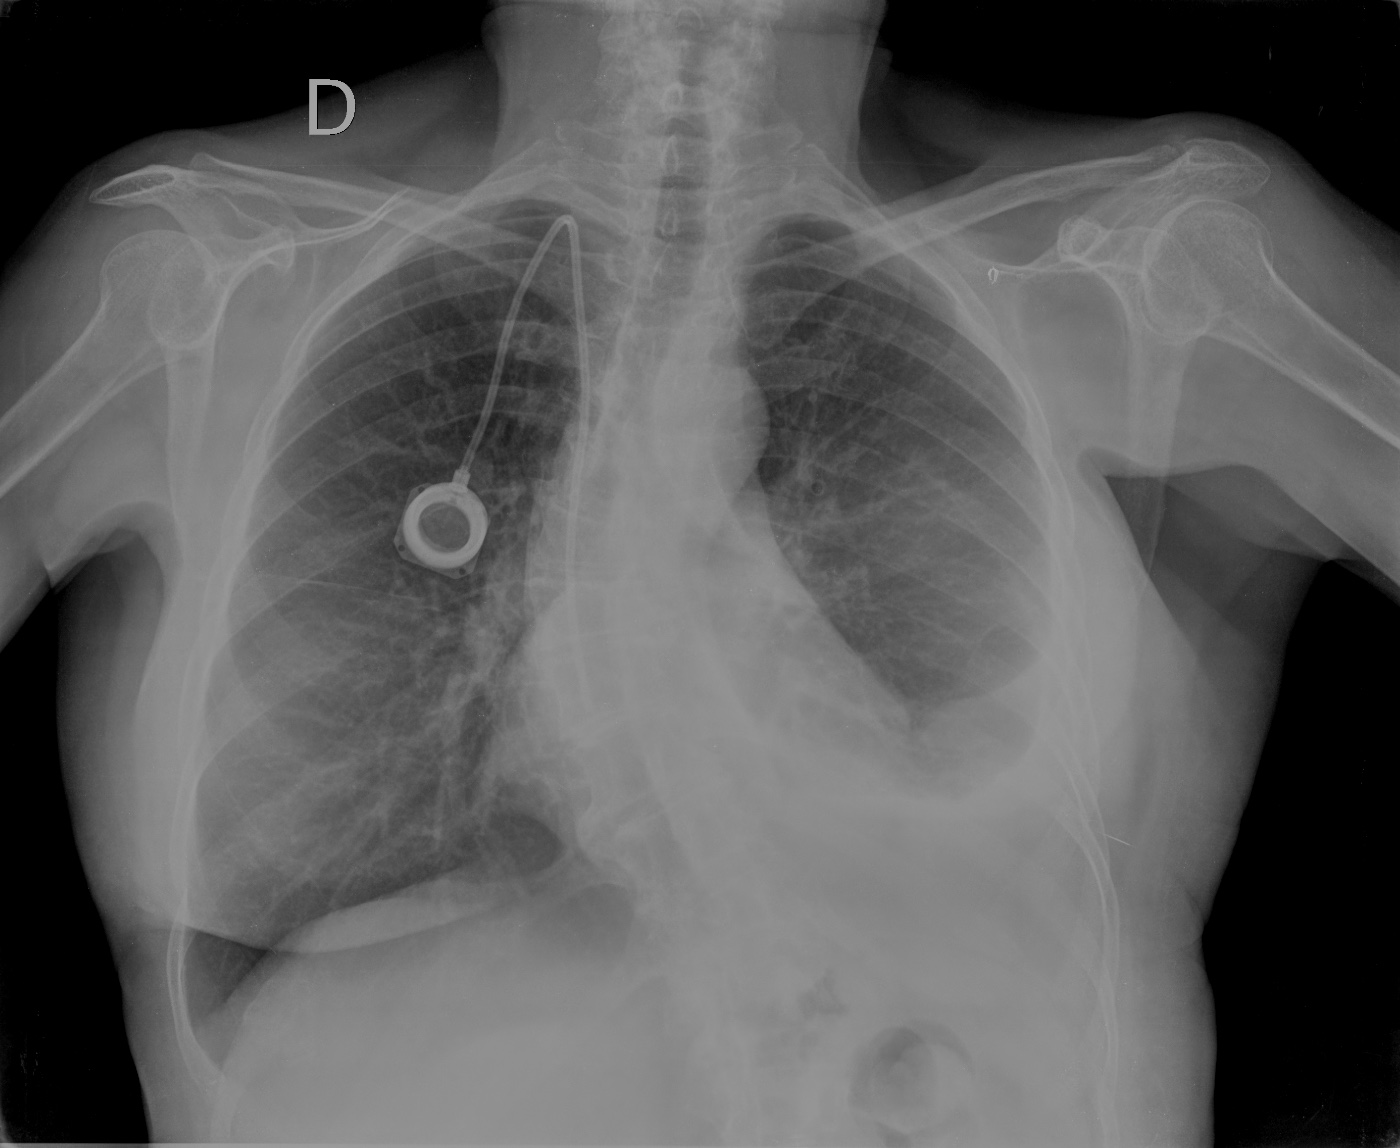

CASO: Operada de cáncer de mama izquierda en revisión.

Hallazgos:

- Prótesis mamaria izquierda (obsevar el aumento de densidad homogéneo y de bordes bien definidos en la placa PA y lateral)

- Parénquimas pulmonares y silueta cardiomediastínica sin alteraciones significativas.